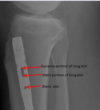

What supplies the inner and outer parts of bone? (blood vessels)

Nutrient artery system supplies inner 2/3

is a high pressure system

Periosteal system supplies outer 1/3

is a low pressure system